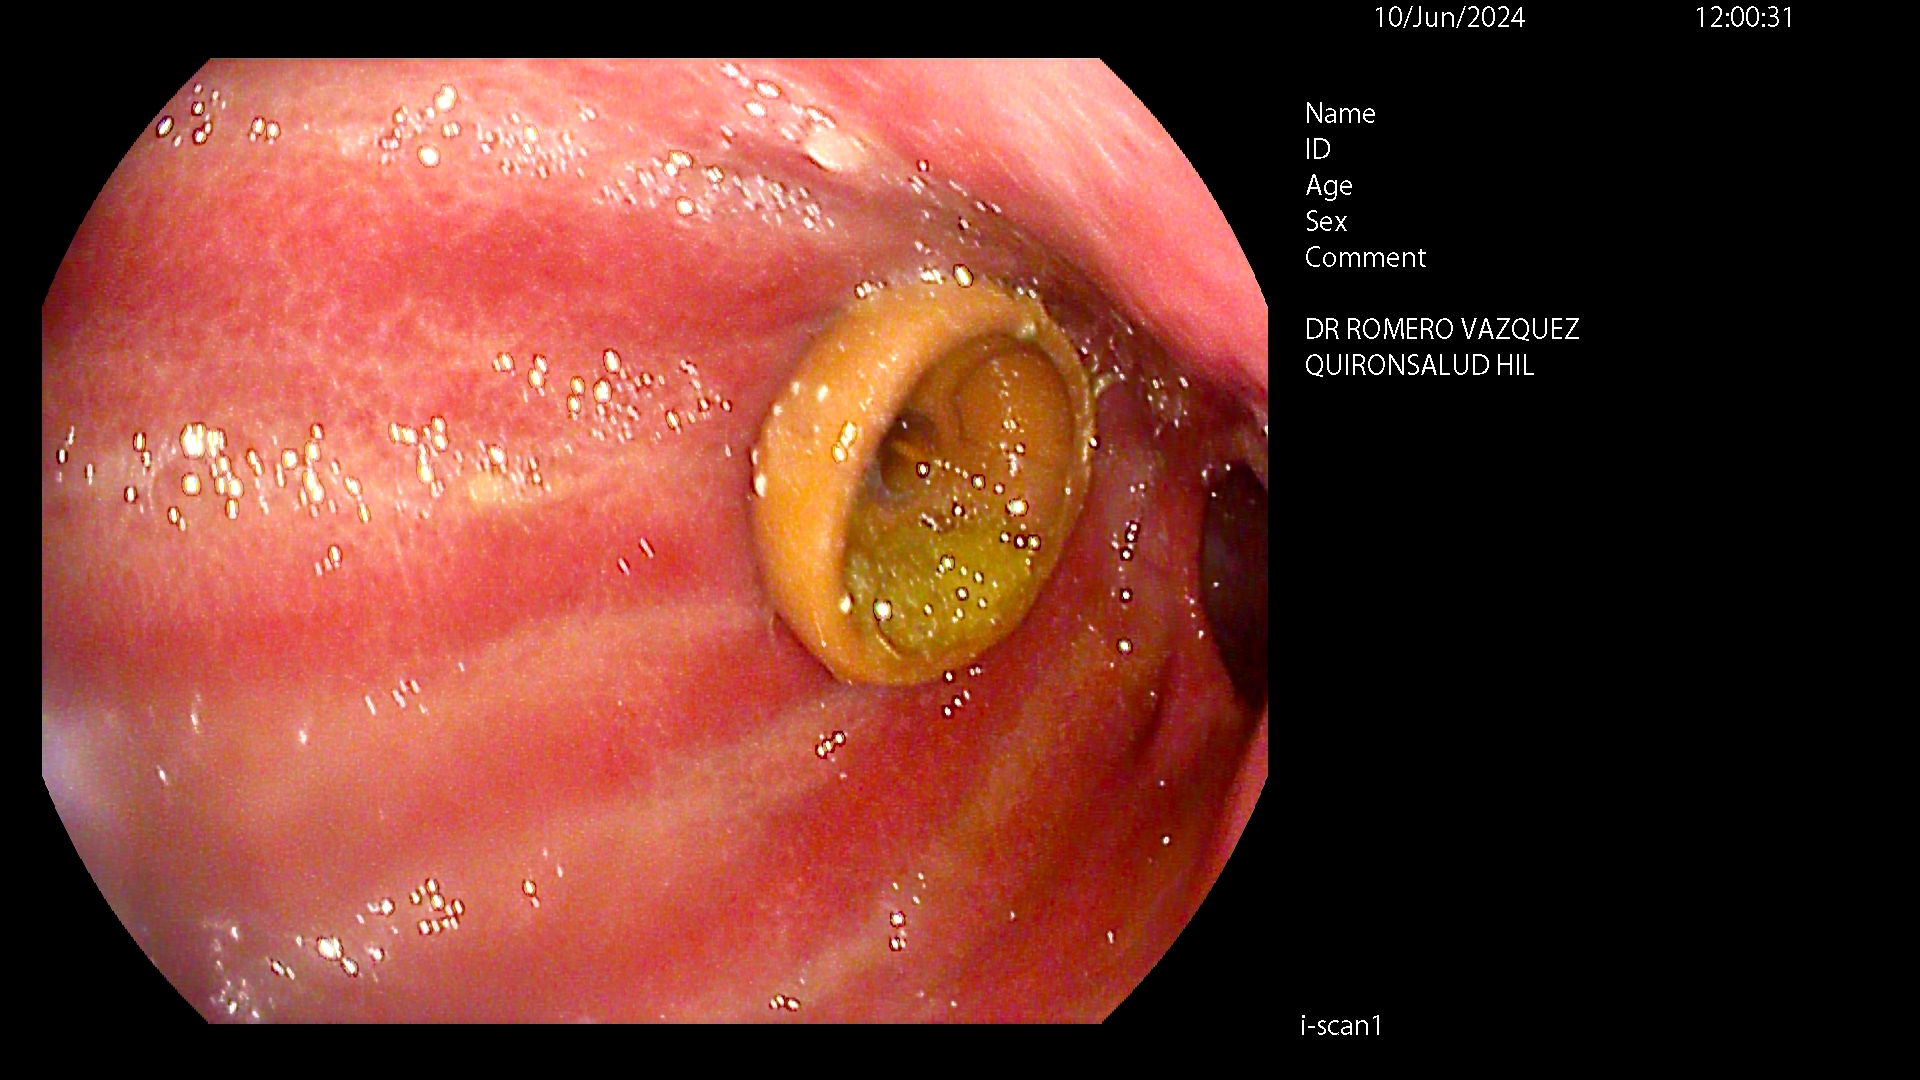

Es una sonda de larga duración precisando sólo recambios, fáciles de realizar en unos 4-6 meses, dependiendo del deterioro propio de la sonda. Normalmente, el primer recambio precisa asistencia endoscópica con sedación profunda y los siguientes no requieren endoscopia ni sedación por anestesista, realizándose de forma ambulatoria.

La sonda queda sujeta por un botón gástrico o balón en el estómago y un disco ajustable sobre la piel.